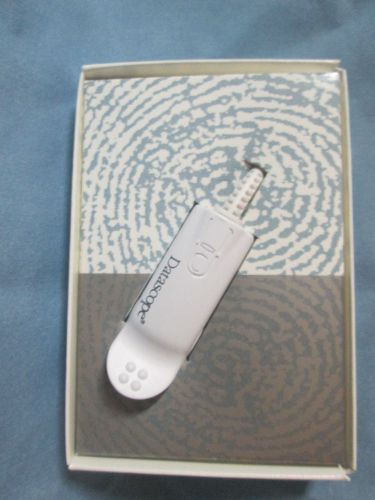

Datascope® Compatible spo2 sensor 0600-00-0026-01 boxed

Datascope® Compatible spo2 sensor 0600-00-0026-01

Datascope® Compatible spo2 sensor 0600-00-0026-01 no boxed